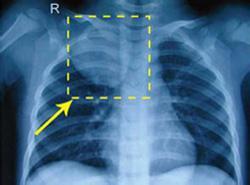

纵隔压迫综合征(mediastinum stressed syndrome)是一组症候群,凡纵隔内任何组织或器官的病变,都可对呼吸道、心血管和食管等产生压迫症状。其病因可为先天性组织异常,或为原发性或转移性肿瘤,也有的由淋巴结炎和脓肿所引起。因受压部位和性质不同,其表现亦不一致。